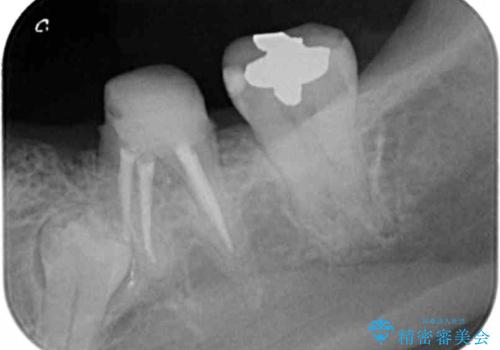

X線写真より、乳歯は抜歯が必要な状態でインプラントは小臼歯の埋伏により難しい状況であったのでブリッジによる補綴を選択しました。

- 26万円(仮歯・ファイバーコア・フルジルコニアクラウン×3) 費用は治療当時の料金となります